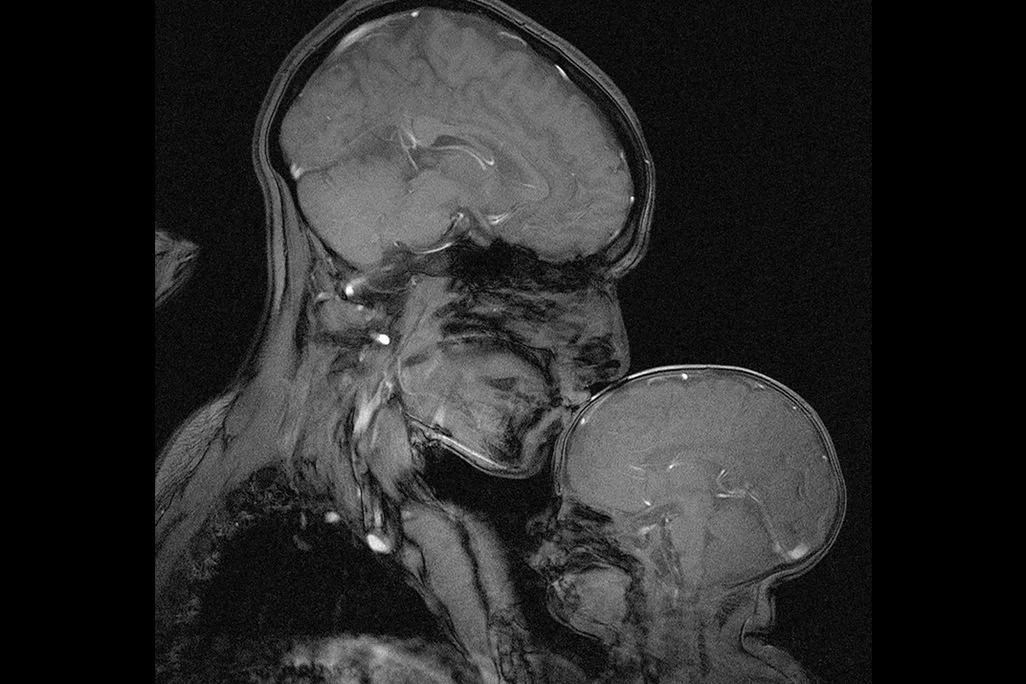

The Pregnant Brain: How Neuroplasticity in Pregnancy and Postpartum Makes Perinatal Therapy The Best Bang For Your Buck

This is your brain on pregnancy